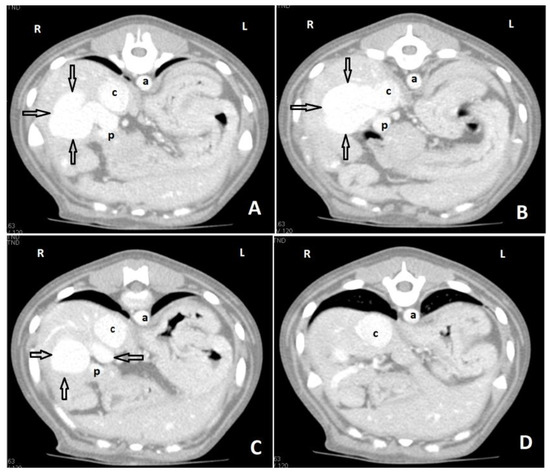

6. Clinical Signs/Physical Examination

9. Diagnostic Imaging